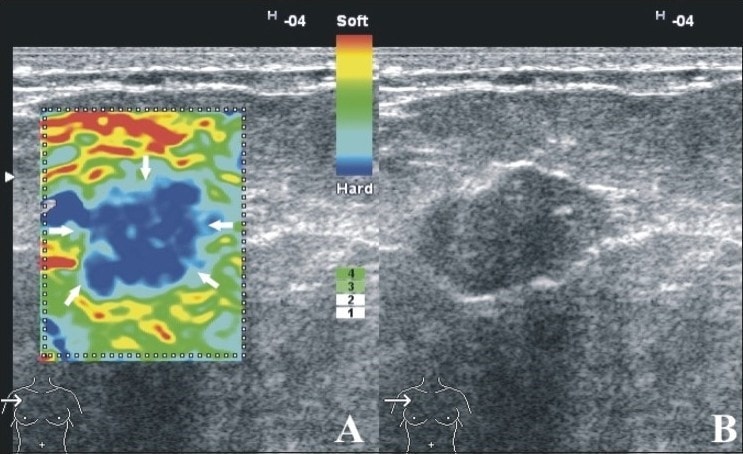

الاستوگرافی یک تکنیک جدید سونوگرافی می باشد که با استفاده از خواص مکانیکی بافت در مقایسه با سونوگرافی ساده اطلاعات بیشتری در مورد ضایعات و تومورها به پزشک می دهد.

الاستوگرافی یک نوع ارزیابی غیرمداخله ای و غیر تهاجمی برای بررسی توده ها می باشد .  این روش بر اساس تفاوت الاستیسیته و درجه سختی توده ها در مقایسه با بافت طبیعی ، میزان احتمال بدخیمی ضایعات را تشخیص می دهد.

بطور مثال توده های سرطانی دربافت پستان یا پروستات سفت تر از بافت های اطرافشان هستند همانند آنچه در بیماری های کبد مثل سیروز کبدی اتفاق می افتد، در نتیجه با توجه به تفاوت سرعت برگشت امواج صوتی سونوگرافی از توده در مقایسه با بافت طبیعی ، روش الاستوگرافی می تواند اطلاعات بیشتری در مورد جنس توده و تومور به پزشک بدهد.